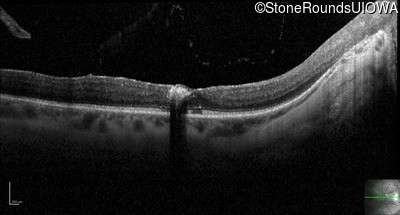

Optical Coherence Tomography - Right - 20/25 sc

Exemplar / OCT Stack

Optical Coherence Tomography - Left - 20/40 sc